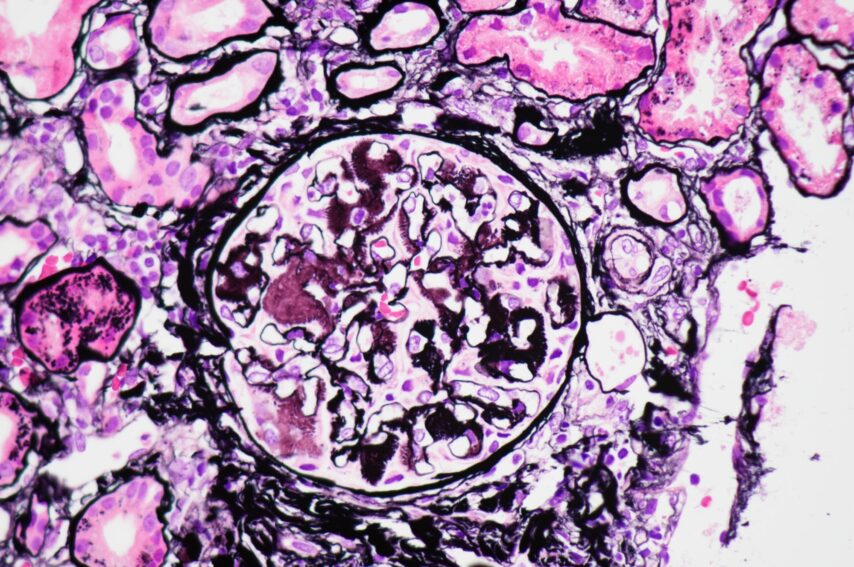

Author: Nisrine Bennani Guebessi, Morocco

Histology

Info:

The image displays glomerular capillary lumens filled with large lymphomatous cells, indicative of intravascular large B-cell lymphoma. Masson’s trichrome stain at 200x magnification.

From:

Nisrine Bennani Guebessi, Morocco

Pathologist and Professor of pathology, department of pathology CHU IBN ROCHD, Casablanca